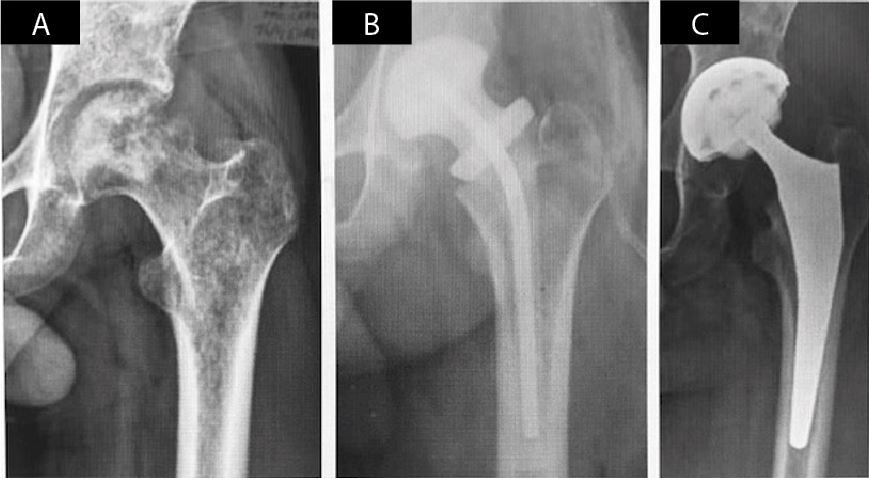

defined as patients with a clinical presentation of severe spontaneous pain that increases with joint motion, load intolerance, fever, erysipelatous inflammation, swelling, altered laboratory parameters (leukocyte count, ESR and CRP), radiological evidence of usually rapid joint line narrowing and later bone destruction (Figure 1), MRI changes and finally, a positive culture in joint aspiration

Patients in group 1 with evolving septic arthritis (9 hips in 8 patients) had hip joint aspiration to identify the causative microorganism. Subsequently, they were treated in two stages. The initial surgical procedure was carried out through an anterolateral approach with extensive synovectomy, resection of the femoral head and acetabular reaming for removal of remaining articular cartilage. Three to six samples for culture and antibiogram were obtained. A hand made (3 hips) or preformed (6 hips) antibiotic (ATB) loaded spacer was placed, generally with Gentamicin and, in case of adding cement, this was mixed with Vancomycin (1 to 3 grams). Patients continued with intravenous antibiotic treatment and then orally for a minimum of 6 weeks, as established by the Infectology Dept. The second stage took place once the laboratory values (ESR and CRP) yielded normal twice, without ATB treatment, with an interval of two weeks between them. Once remission of infection was ascertained, final reimplantation was performed. The type of prosthesis to be used (uncemented, hybrid or cemented) was selected according to age, functional demand, and bone quality. Systemic AB were used for 24 hours only and in cases of hybrid or cemented implants, ATB added to cement was used as infection prophylaxis (no more than 1 g per dose of cement), but not as a treatment for the infection since the infection was considered resolved before performing the joint replacement procedure. (Figure 1 A to C).